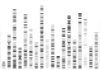

Executive dysfunction can create symptoms like:

- Difficulties with initiating, organising and carrying out activities

- Rigidity in thoughts and actions

- Poor problem solving

- Impulsivity

- Mood disturbances

- Difficulties in social situations

- Difficulties with memory and attention